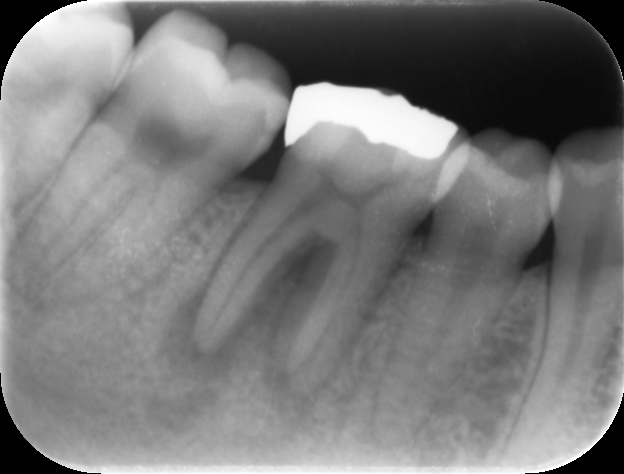

| 治療前レントゲン | 治療前CT |

|---|---|

| 治療前レントゲン |

|---|

| 治療前CT |

初診時レントゲンおよびCT画像です。根尖部には根尖病変と思われる黒いX線透過像を認めます(矢印)。

歯冠部には、歯髄に近接するレジン充填と思われる白いX線不透過像を認めます。深い虫歯治療後に歯髄壊死を生じたと推察されます。